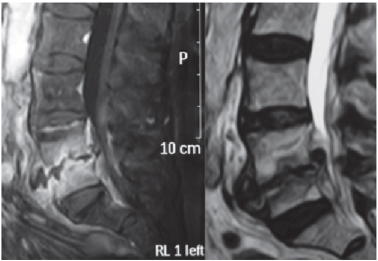

Sobre a entidade clínica representada na figura abaixo, é CORRETO afirmar que